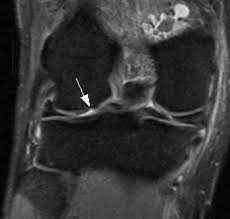

Medial condyle of femur from wikipedia, the free encyclopedia the medial condyle is one of the two projections on the lower extremity of femur, the other being the lateral condyle. The lateral condyle was involved in 44 % and the medial condyle in 12 %. Palpable as a hard, rounded bump to the inside of either knee joint, they are one of two condyles at the bottom of each leg bone, the other being the lateral femoral condyle. This adaptable graft option is most commonly used with oats or shell techniques to restore cartilage in the knee, but can also be used to for cartilage restoration of other joints. In a review of 79 patients with this disease, performed to establish guidelines f … The medial femoral condyle is supplied by a plexus of vessels from the descending genicular artery and the medial superior genicular artery. The medial condyle is larger than the lateral (outer) condyle due to more weight bearing caused by the centre of mass being medial to the knee. Root tear (radial tear) of the medial meniscus mild or moderate knee arthritis According to the hospital for special surgery, the medial femoral condyle is the inside of the knee, and health issues dealing with it can be treated. Osteonecrosis of the medial femoral condyle can be treated in a variety of ways depending on the stage of the disease. The medial condyle is named for its location on the inside of the knee, closer to the midline of the body, while the lateral condyle is found on the outside of the knee, away from the midline of the body. In the knee, chondromalacia is usually related to injury, overuse of the knee, and poorly aligned muscles and bones around the knee joint. Your knee mri will often show a:

Of the six patients who had suffered an isolated fracture of their medial condyle, four of the patients had their fractures diagnosed on the first visit. The lateral condyle was involved in 44 % and the medial condyle in 12 %. It acts to support a significant amount of the patient's body weight. Cartilage can be focally damaged, producing a pot hole in the joint surface, when the knee ligaments are injured. Osteonecrosis of the medial femoral condyle presents as a sudden onset of pain on the medial side of the knee. A bone fracture at this location is termed a femoral condyle fracture. The femoral condyle is a thickened area of the femur just above the knee. One presumed mechanism of injury is a stieda fracture (avulsion injury of the medial collateral ligament at the medial femoral condyle). Root tear (radial tear) of the medial meniscus mild or moderate knee arthritis Coronal plane fracture of the lateral femoral condyle. The lesions were located on the medial femoral condyle in 8 (72.7%) cases and on the medial tibial plateau in 3 cases (27.3%). The medial femoral condyles are the bony protrusions on the inside edge of the bottom of the femur bone in each thigh. Based on the patient's antalgic gait and radiographic findings, the patient was instructed on the proper use of crutches and referred to an orthopaedic surgeon for appropriate management.

Methods sixteen knees with a small medial femoral. The lesions were located on the medial femoral condyle in 8 (72.7%) cases and on the medial tibial plateau in 3 cases (27.3%). Radiographic features it is almost always unilateral, usually affects the medial femoral condyle (but can occasionally involve the tibial plateau 9) and is often associated with a meniscal tear. In the knee, chondromalacia is usually related to injury, overuse of the knee, and poorly aligned muscles and bones around the knee joint. It acts to support a significant amount of the patient's body weight. Normal irregular ossification of the femoral condyles was present in 66% of the boys and 44 % of the girls 1 in a review of knee radiographs of 147 healthy, asymptomatic children between the ages of 3 and 13 years. The inner side of the knee or the medial femoral condyle is the most common area for a cartilage defect. A bone fracture at this location is termed a femoral condyle fracture. Palpable to either side of the knee joint when it is bent, they are known specifically as the medial and lateral femoral condyles. If there is a fracture (break) in part of the condyle, this is known as a fracture of the femoral condyle. Primary osteonecrosis of the femoral condyle shares several features with insufficiency fractures, including predominance in elderly women with factors responsible for mechanical stress (varum, obesity, trivial trauma), mechanical pain, and increased radionuclide uptake. An imbalance of the muscles around the knee (some muscles are weaker than others.) overuse (repeated bending or twisting) of the knee joint, especially during sports. Sagittal plane fracture of the medial femoral condyle.